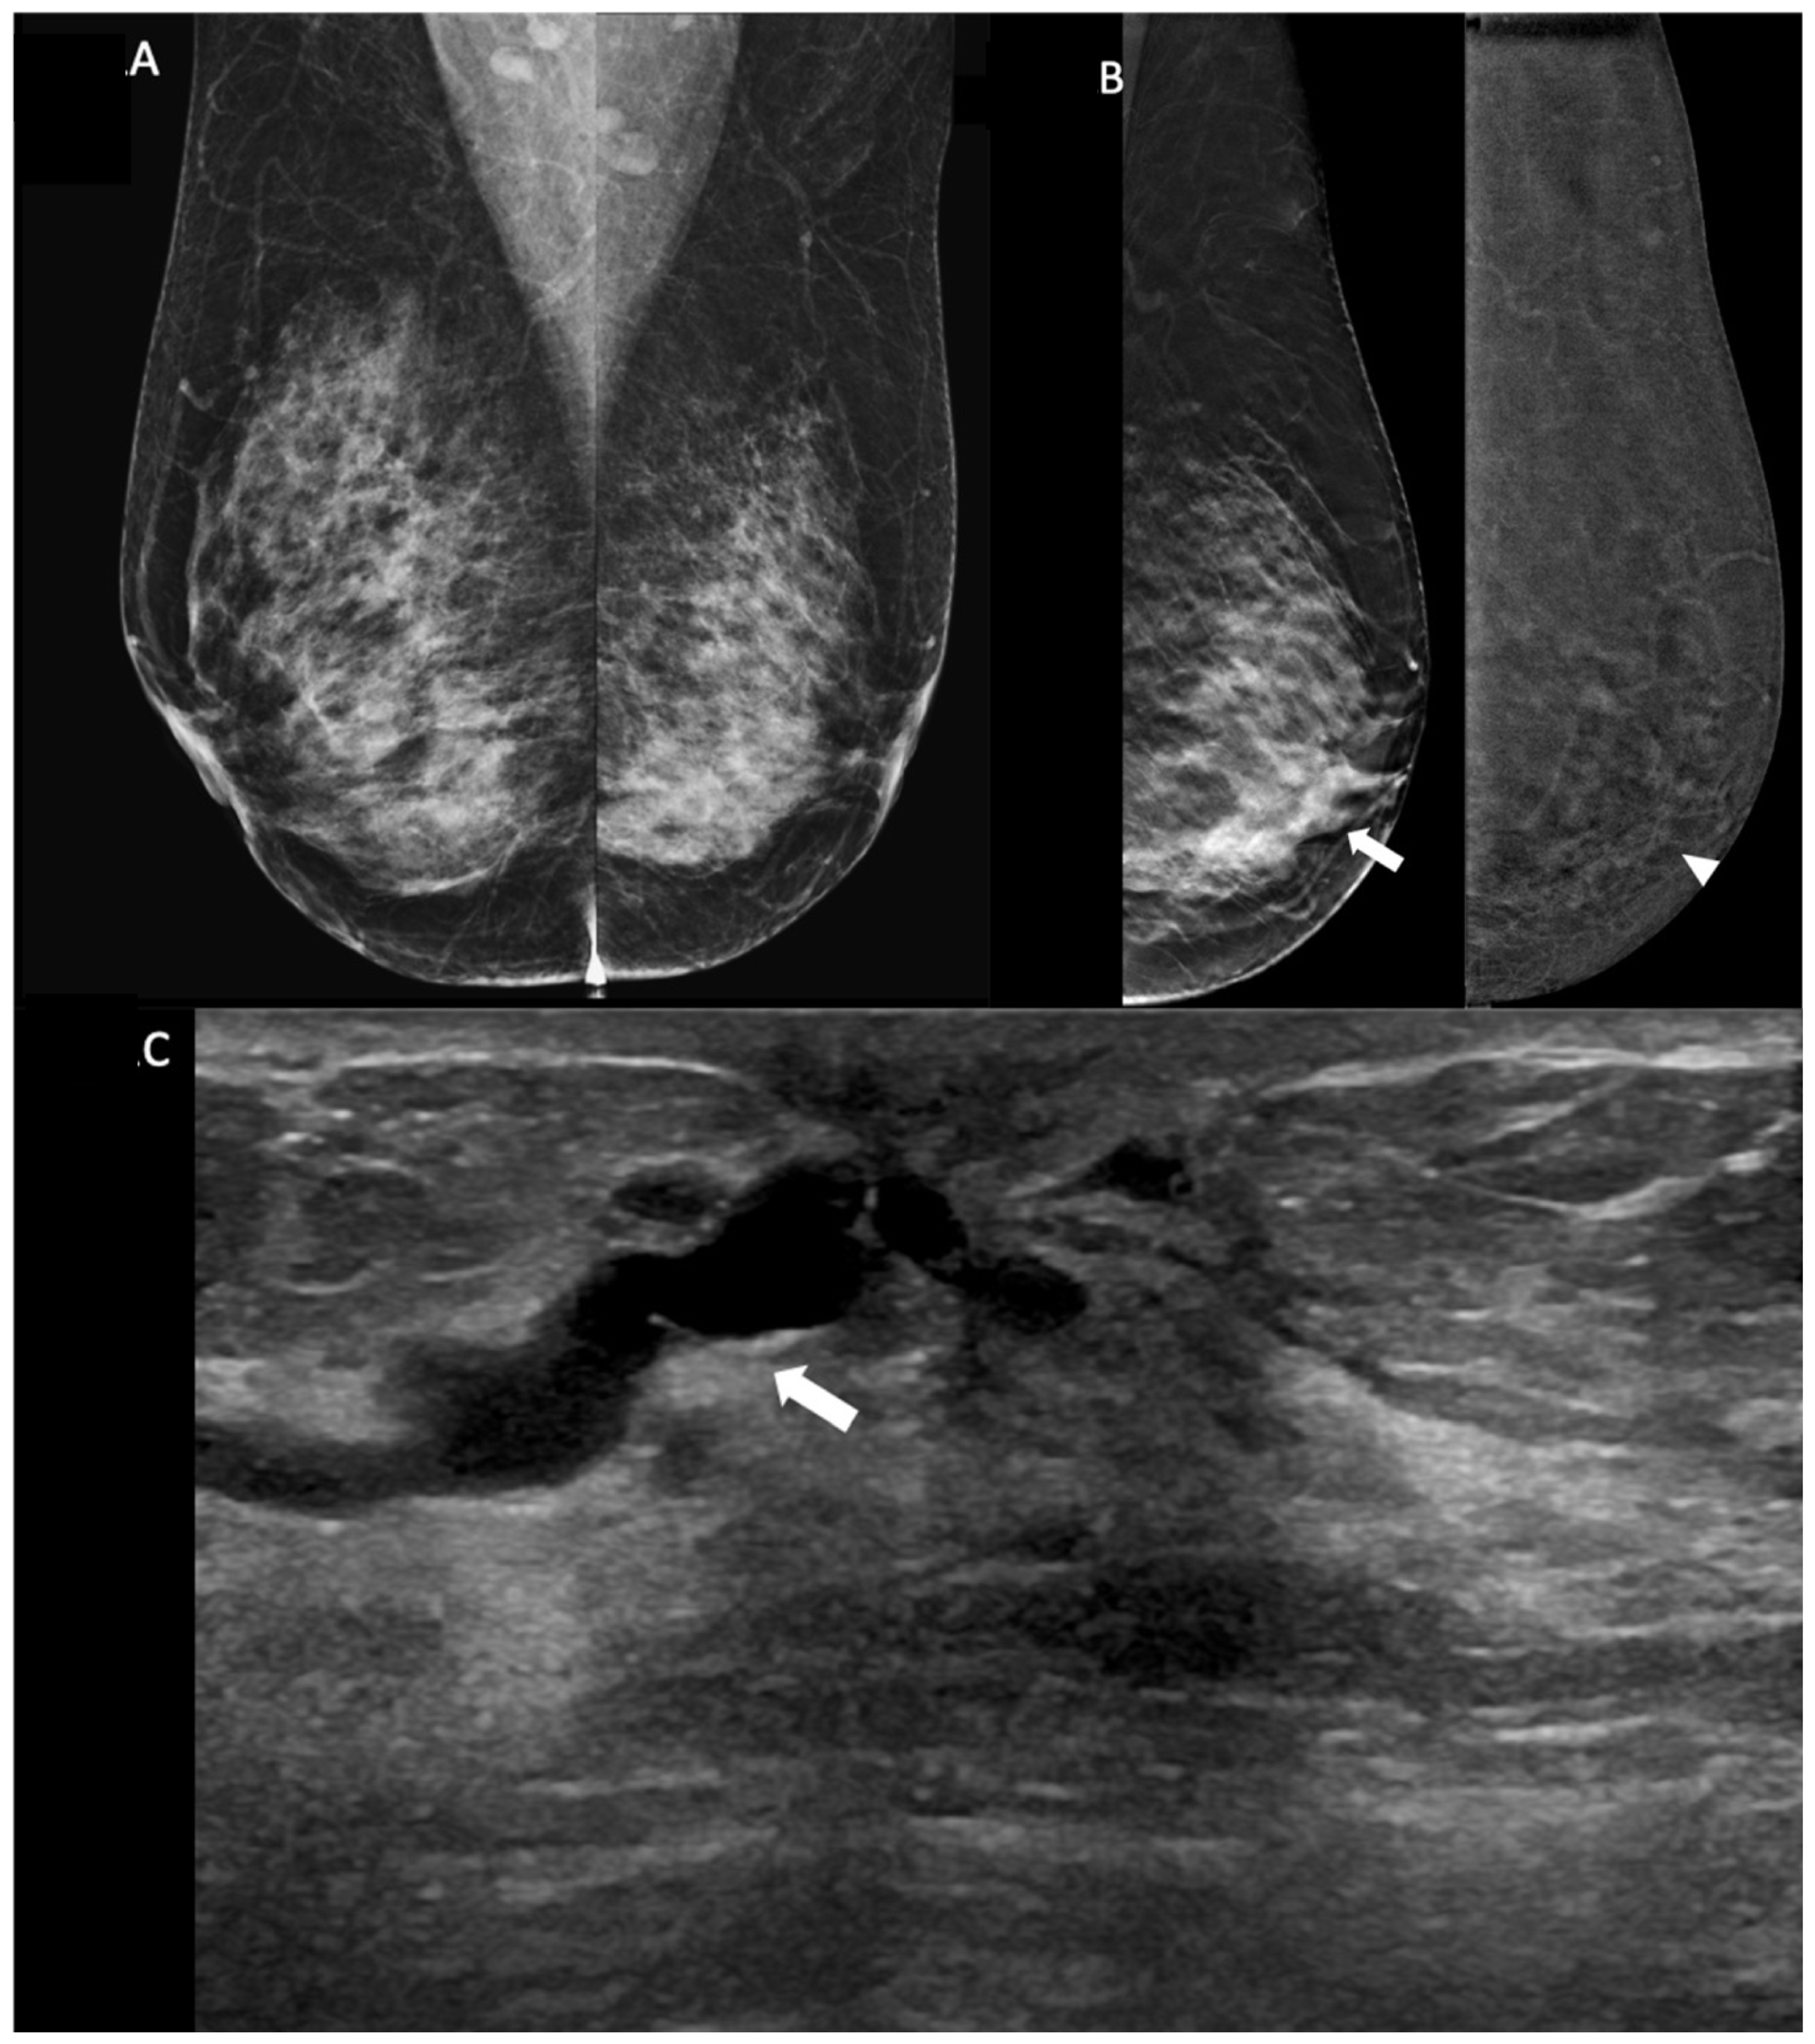

4.2. Benefits of CEM and Clinical Applications

4.3. Lesion Conspicuity

4.4. Morphpological Characteristics